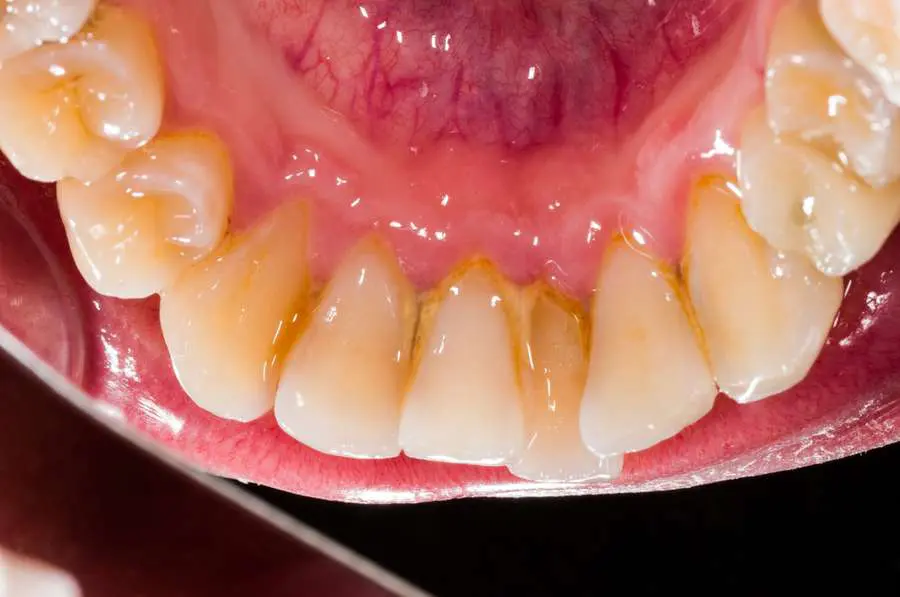

L’azione negativa che il fumo esercita sui denti è in qualche modo più visibile e più nota; parliamo delle macchie e della colorazione scura del tartaro. Pìù rara è invece, essenzialmente nei grandi fumatori , la discromia da fumo, cioè una ipercolorazione grigio nera interna alla sostanza dentale. In questo caso non è sufficiente una semplice seduta di igiene orale ma occorre, per eliminare la colorazione scura, una procedura di sbiancamento (da preferire su tutte la cosiddetta tecnica di sbiancamento domiciliare notturno).